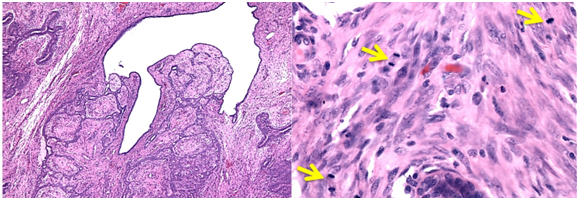

A 47year-old woman with history of a long standing palpable mass on the left breast, which was biopsied on 2006 resulting in hamartoma. She had first degree familiar history of breast cancer with her mother diagnosed younger than 50 \years of age and who later on died of that cause. The patient presented to our office, in June 2016 for progressive growth of her breast tumour. At examination her breasts were fibrous, with a palpable firm and mobile breast mass, not fixed to skin, of 8x6x5cm on the left LIQ, and another large, soft and well defined mass in left LOQ and UOQ of 10x10x5cm, There were no palpable masses in the axilla. On mammography there was a radiolucid well defined breast mass in the left LOQ and UOQ, which was stable in size and shape regarding prior mammogram of twoyears. A new dense, oval and partially defined breast mass was evident in the LIQ (Figure 1). The latter on breast ultrasound corresponded with a hypoechoic and heterogenous nodule with partially defined margins, which measured approximately 7cm. The first lesion was heterogenous and hyperechoic, measured more than 8cm, and was the previously biopsied nodule (Figure 2). She later on underwent a breast MRI that showed a round mass in the LIQ, which was hyperintense in T2, hypointense in T1, had a homogenous enhancement with a plateau curve. In the LOQ there was a well-defined mass, which was heterogenous with fibrous and fatty tissue, and did not enhance with gadolinium (Figure 3). A core biopsy of the two masses was then performed, demonstrating a biphasic fibro-epithelial lesion compatible with a PT at the LIQ, and fibrocystic changes and intraductal hyperplasia without atypia at the LOQ. On August 2016, the patient underwent a partial mastectomy, without incidents, and was sent home on the subsequent day (Figure 4). The definitive biopsy demonstrated that the tumour at the LIQ corresponded to a malignant PT (Figures 5) (Figure 6), and that the LOQ mass was a large breast hamartoma (Figures 7 & Figure 8). Posteriorly, she received 25 radiotherapy fractions, without major adverse effects. She was recently controlled with breast ultrasound and MRI that showed no residual breast lesions.

Figure 6 Phyllodes tumour histology with signs of malignancy. A) Microscopic typical appearance. B) The arrows show several mitosis in a microscopic field (haematoxylin - eosin X100, original magnification).